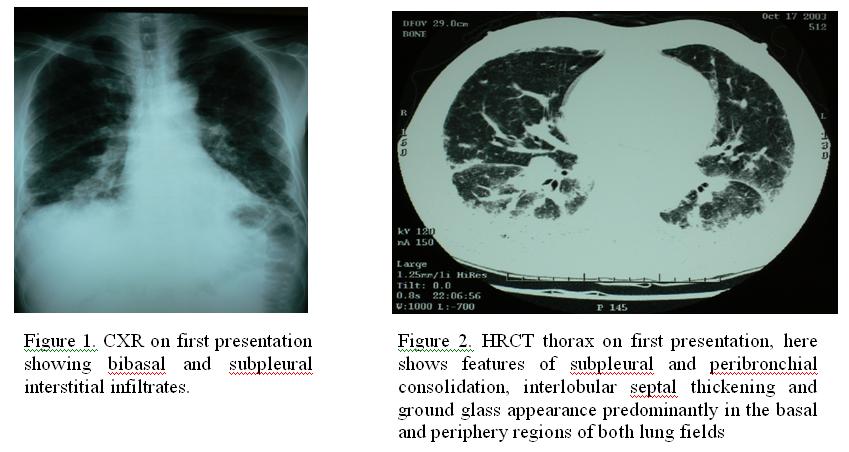

Chest radiograph showed bibasal and subpleural interstitial infiltrates (Figure 1) , while HRCT thorax demonstrated subpleural and peribronchial consolidation, interlobular septal thickening and ground glass appearance predominantly in the basal and periphery regions of both lung fields (Figure 2). Platelet count was 50, other blood count, renal and liver functions were normal. Arterial blood gas showed hypoxia. Sputum grew xanthomonas maltophilia, AFB smear was negative. Tests for HIV, coronavirus and immune markers were also negative. Bone marrow examination was normal. Spirometry showed restrictive defects with impaired diffusing capacity.